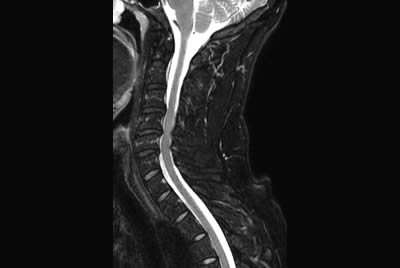

Comprehensive Cervical Spine imaging at 3.0T